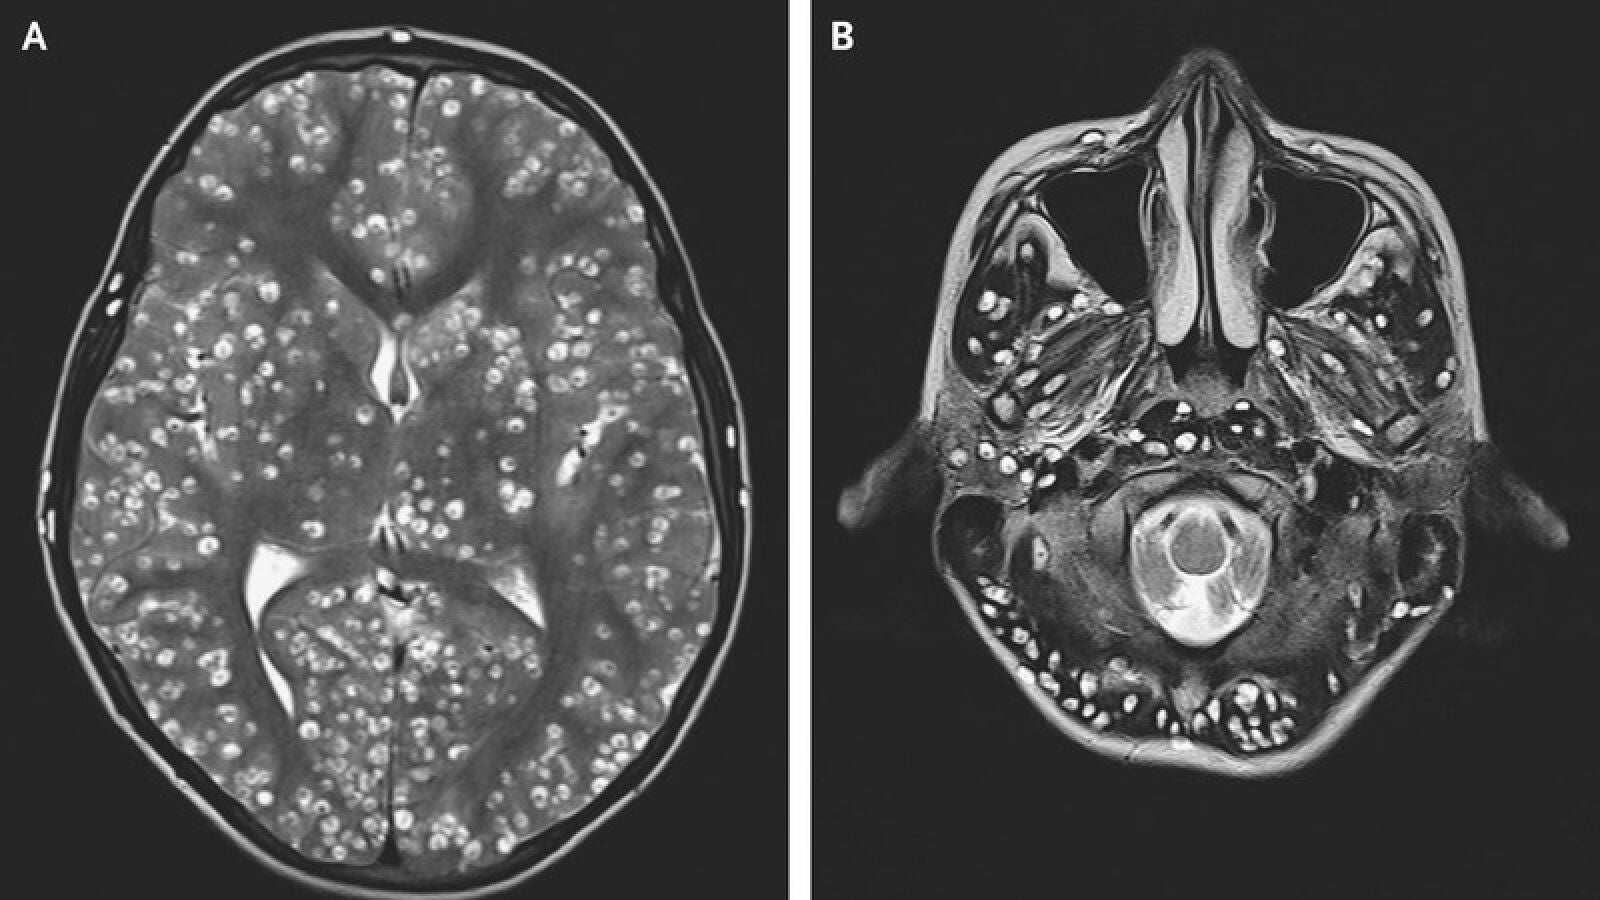

La joven se sometió a una operación para extirpar el tumor. Durante la cirugía el neurocirujano vio "una lesión bien encapsulada y firme que era ovoide". "Parecía un huevo de codorniz", afirma Rasouli. En ese momento el médico descubrió que no se trataba de un tumor cerebral. El doctor cogió una muestra de la lesión extraída, la colocó bajo un microscopio quirúrgico y descubrió que lo que tenía era una tenia de cerdo.